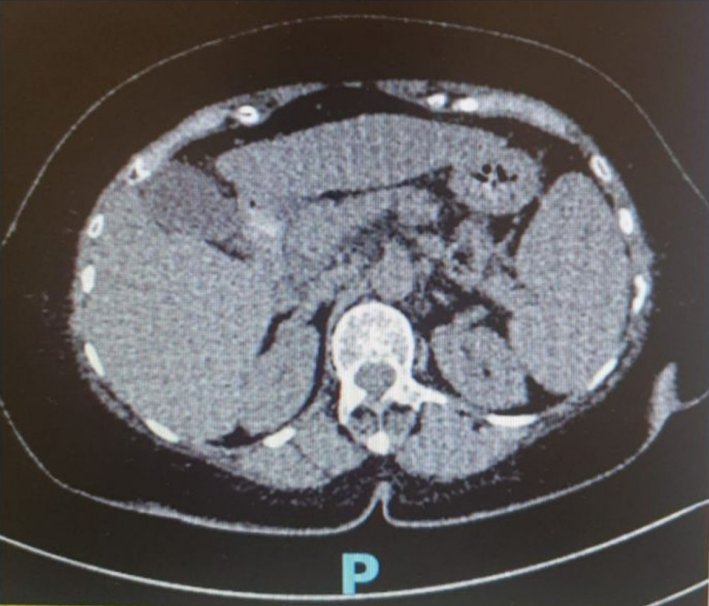

病史摘要:78岁女性患者,因呕血、黑便3天就诊。患者肥胖,饮食作息不规律。4年前反复出现上腹部不适、腹胀,检查提示慢性肝病伴肝脏弥漫性脂肪变性、脾大、脾静脉扩张,门脉高压性胃病、多发性胃溃疡,无消化道出血史。无显著家族病史,否认饮酒、吸烟。 诊疗过程:查体见贫血貌、上腹部压痛、脾大,伴少量腹水。实验室检查显示贫血、血小板减少、低蛋白血症、肝功能受损、凝血时间延长、随机血糖及糖化血红蛋白升高